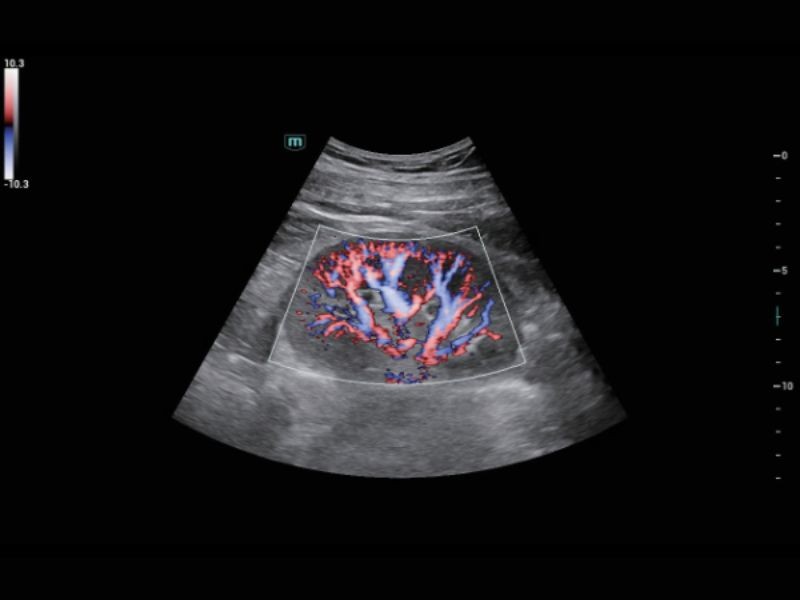

Solução de saúde para mulheres

Cena Inteligente 3D

Solução obstétrica inteligente full-stack com tecnologia ZST⁺

FLC inteligente 2D / 3D

Contagem e medição automática de folículos no modo 2D/3D